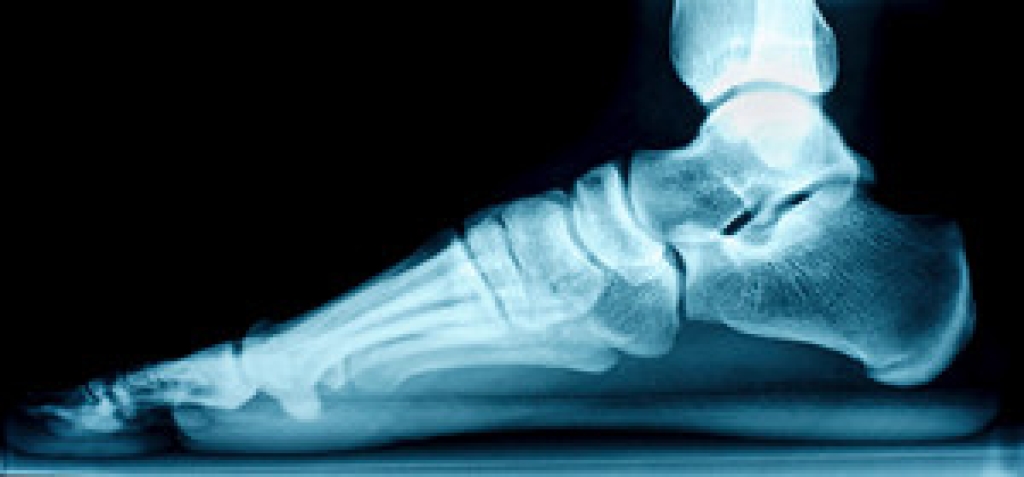

The Achilles tendon is a band of fibrous tissue that connects your calf muscles to your heel bone. Though this tendon is tough, it can tear or rupture during physical activity. A ruptured Achilles tendon can cause many symptoms, including a sharp, sudden pain at the back of the ankle, difficulty walking, weakness, and an inability to raise the injured foot. Some people are able to walk or continue playing sports with a ruptured Achilles tendon due to the surrounding muscles compensating. However, this can make the injury worse. A rupture can be treated conservatively or with surgery. Conservative treatment typically involves immobilizing the injured leg with a cast to allow it to heal. Surgery repairs the ruptured tendon. If you believe that you may have ruptured your Achilles tendon, it is strongly suggested that you seek the care of a podiatrist.

The Achilles tendon is a tendon that connects the lower leg muscles and calf to the heel of the foot. It is the strongest tendon in the human body and is essential for making movement possible. Because this tendon is such an integral part of the body, any injuries to it can create immense difficulties and should immediately be presented to a doctor.